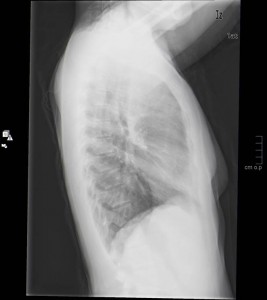

La ecografía es de primera elección al ser fácil de hacer, inocua para el paciente y de bajo coste. La PAAF también se realiza en primera instancia por su rapidez y porque da una información objetiva del tejido a estudio. La rx de tórax es una prueba muy fácil de hacer, de baja radiación y que aporta gran cantidad de información relevante.